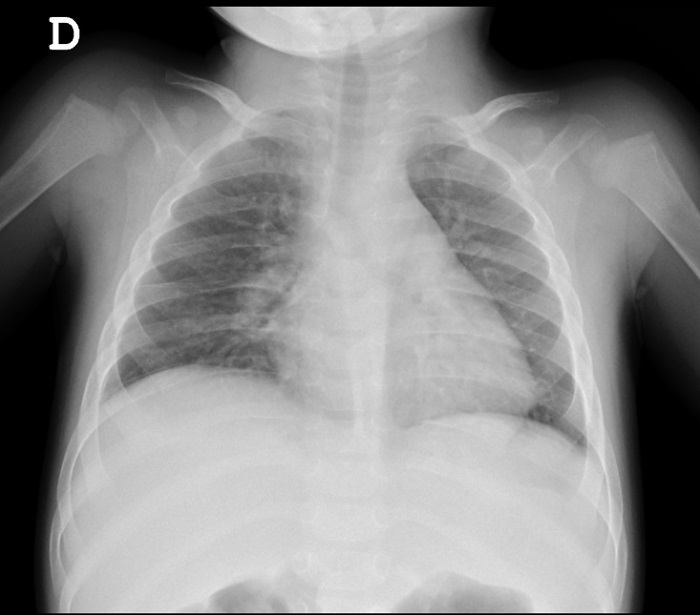

• Radiografía de tórax.